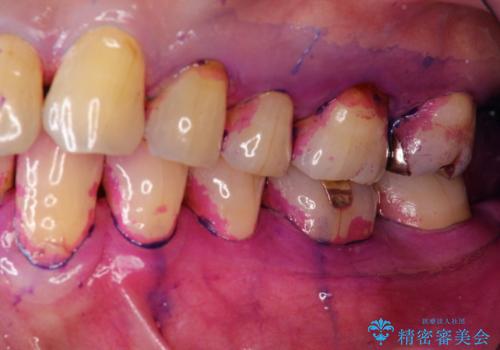

- 2カ月ごとにメンテナンスにいらしている方です。染め出しをしての歯磨きチェックとPMTC30分コースを行いました。

染め出し液を使ってプラークを染め出すことにより、普段の歯みがきで磨き残している場所を目で確かめることができます。